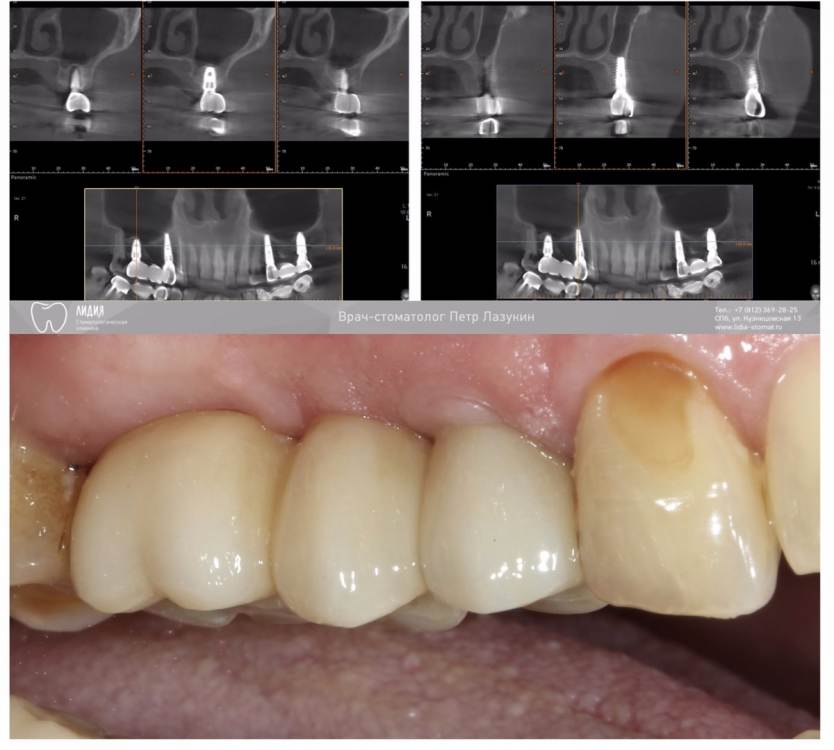

pit Опубликовано 28 октября, 2021 Автор Поделиться Опубликовано 28 октября, 2021 21 минуту назад, annda сказал: Просто по снимку кажется,что высота юбки абатмента на шестерке достаточно низкая. Видимо,про это коллега и спрашивал Что такое юбка абатмента? 14-16 ДЦ мостовидный протез с винтовой фиксацией на титановых основаниях Ссылка на комментарий

АнтонТЛТ Опубликовано 28 октября, 2021 Поделиться Опубликовано 28 октября, 2021 1 час назад, pit сказал: Что такое юбка абатмента? 14-16 ДЦ мостовидный протез с винтовой фиксацией на титановых основаниях Трансгингивальная часть титанового основания. 1 Ссылка на комментарий

pit Опубликовано 28 октября, 2021 Автор Поделиться Опубликовано 28 октября, 2021 14 часов назад, АнтонТЛТ сказал: Трансгингивальная часть титанового основания. Понятно. Трансгингивальная у основания импланта 16 зуба менее 3мм. С точки зрения идеальной позиции импланта-я ошибся. Ссылка на комментарий